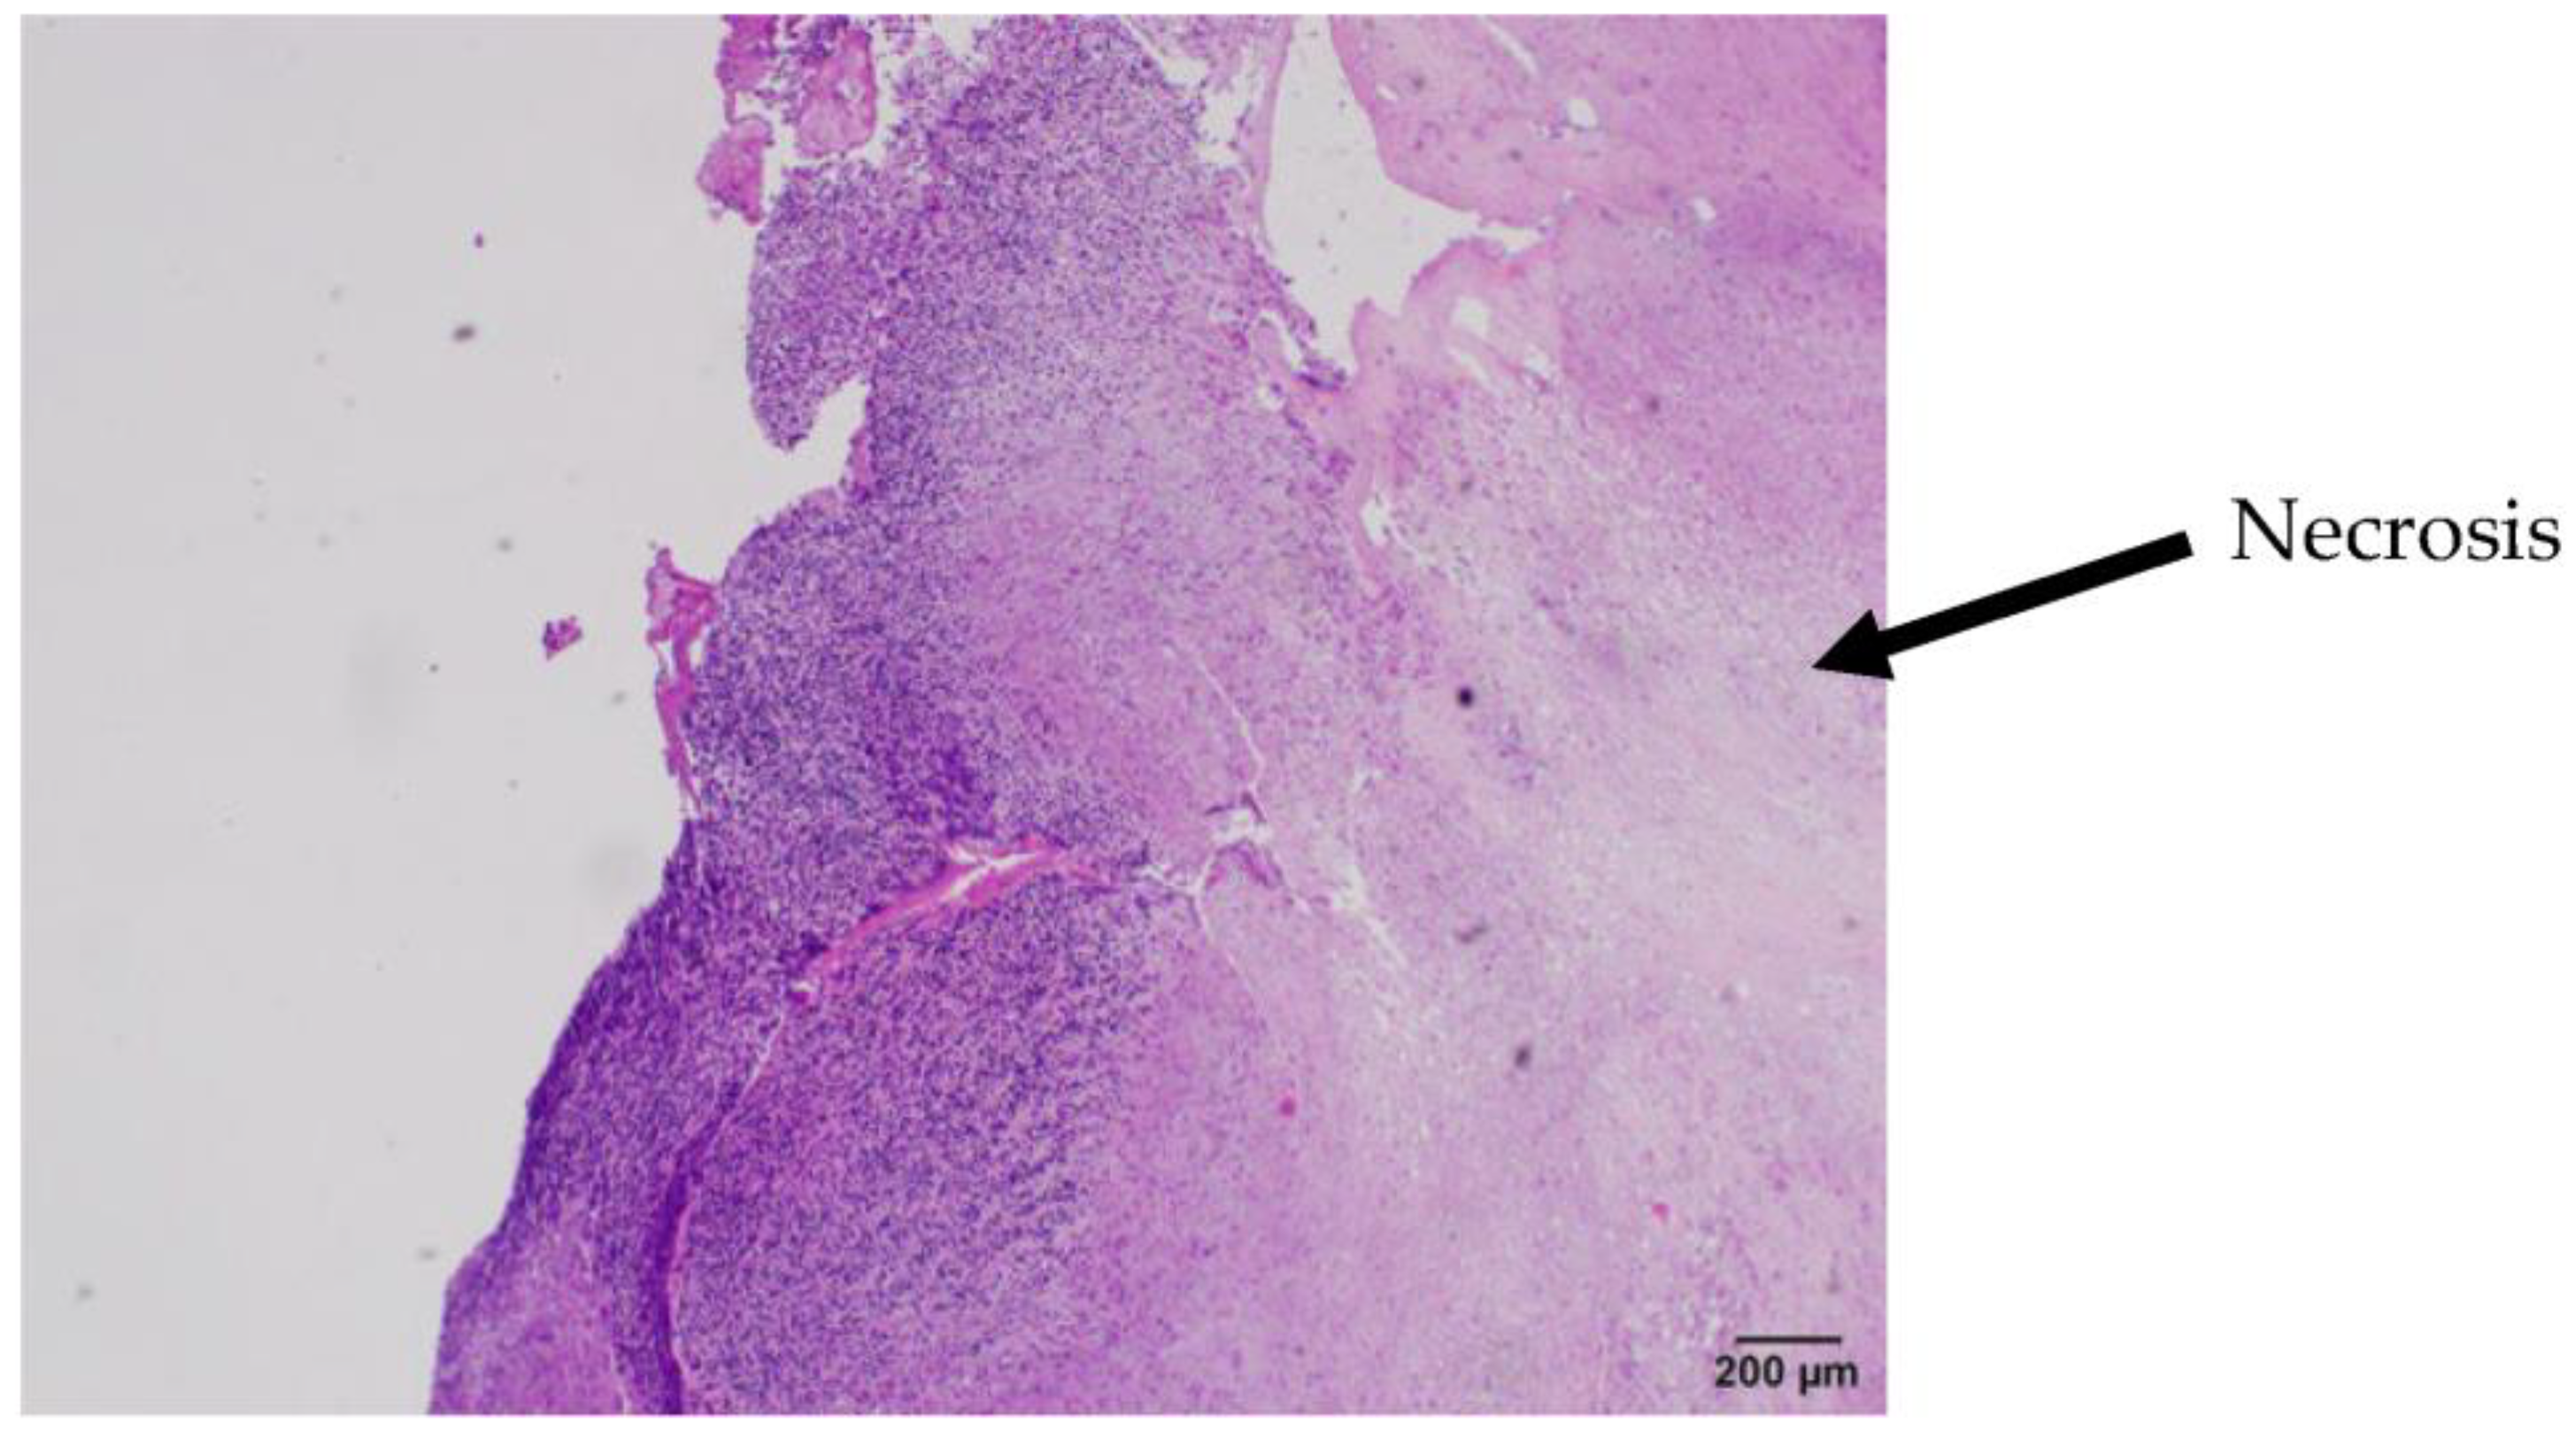

2. Case